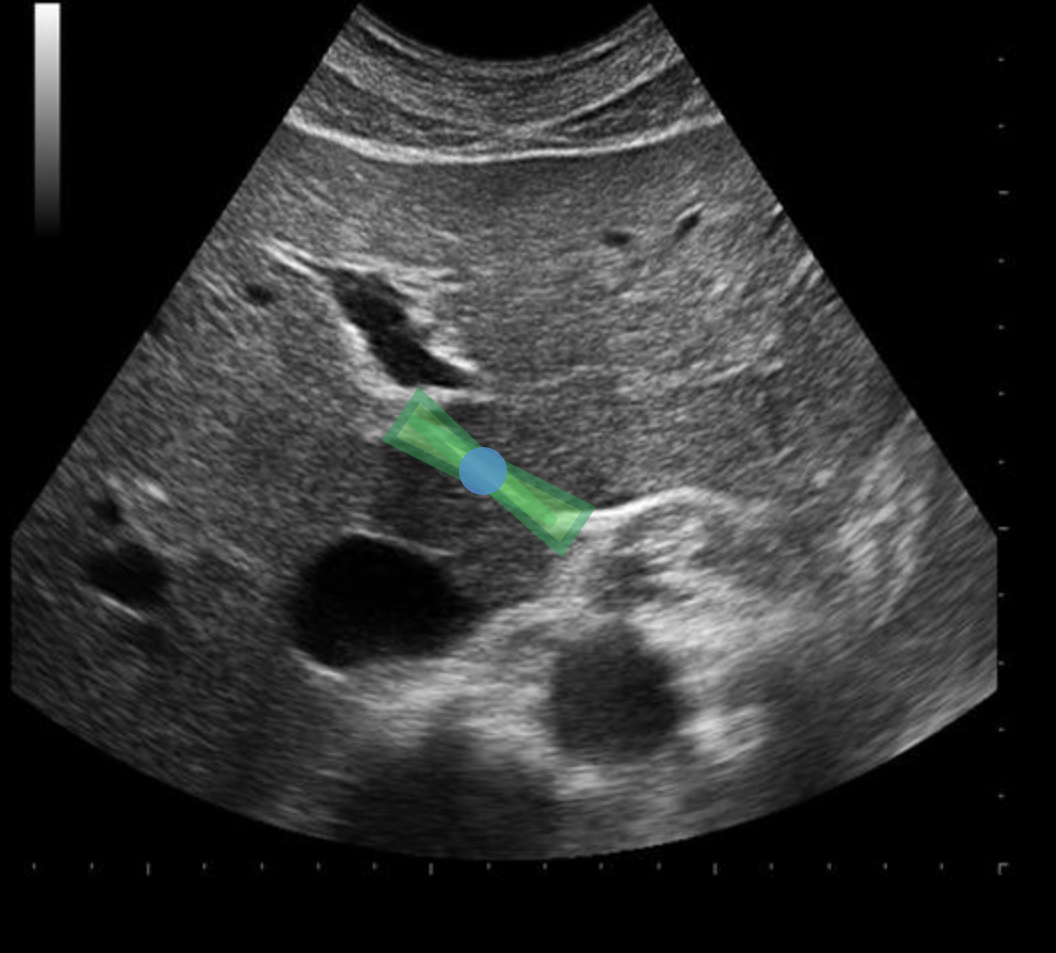

During an abdominal ultrasound, a 4mm circular anechoic structure is identified at the posterior portion of the pancreas head. Color flow is not identified in the structure. What is it?

common bile duct

Use your mouse to place your cursor over the main lobar fissure and click to mark the structure.

Use your mouse to place your cursor over the superior mesenteric vein and click to mark the vessel. If the vessel is not demonstrated on the image, mark the purple box that says "Not demonstrated on the image".

Use your mouse to place your cursor over the left portal vein and click to mark the structure.

Use your mouse to place your cursor over the main portal vein and click to mark the vessel.

Use your mouse to place your cursor over the hepatic artery and click to mark the vessel.

Use your mouse to place your cursor over the main portal vein and click to mark the vessel.

Use your mouse to place your cursor over the common bile duct and click to mark the vessel. If the vessel is not demonstrated on the image, mark the purple box that says "Not demonstrated on the image".